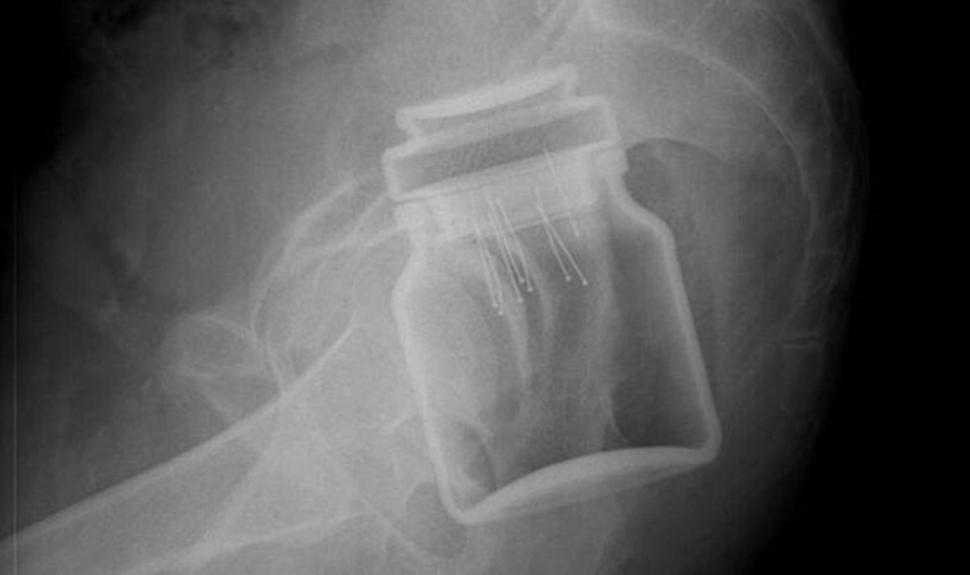

"S-a încercat scoaterea obiectului pe aceeaşi cale, însă a fost imposibil, existând pericolul de a se sparge în interior. Fiind vorba de o zonă puternic vascularizată, era pericolul unei hemoragii masive şi deces. Borcanul, la fel ca şi paharul de anul trecut, era blocat în zona rectului, astfel că s-a intrat chirurgical şi a fost scos prin abdomen", a precizat un medic chirurg de la Spitalul Judeţean de Urgenţă "Mavromati".